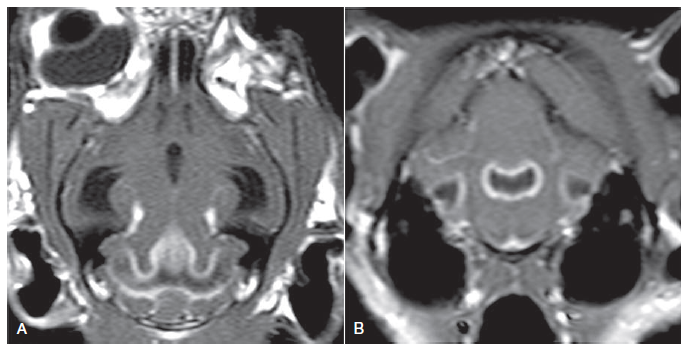

How would you describe this enhancement and what disease could it be?

Marked enhancement of the pachymeninges/dura but not of the sulci

Pachymeningitis (such as idiopathic hypertrophic)